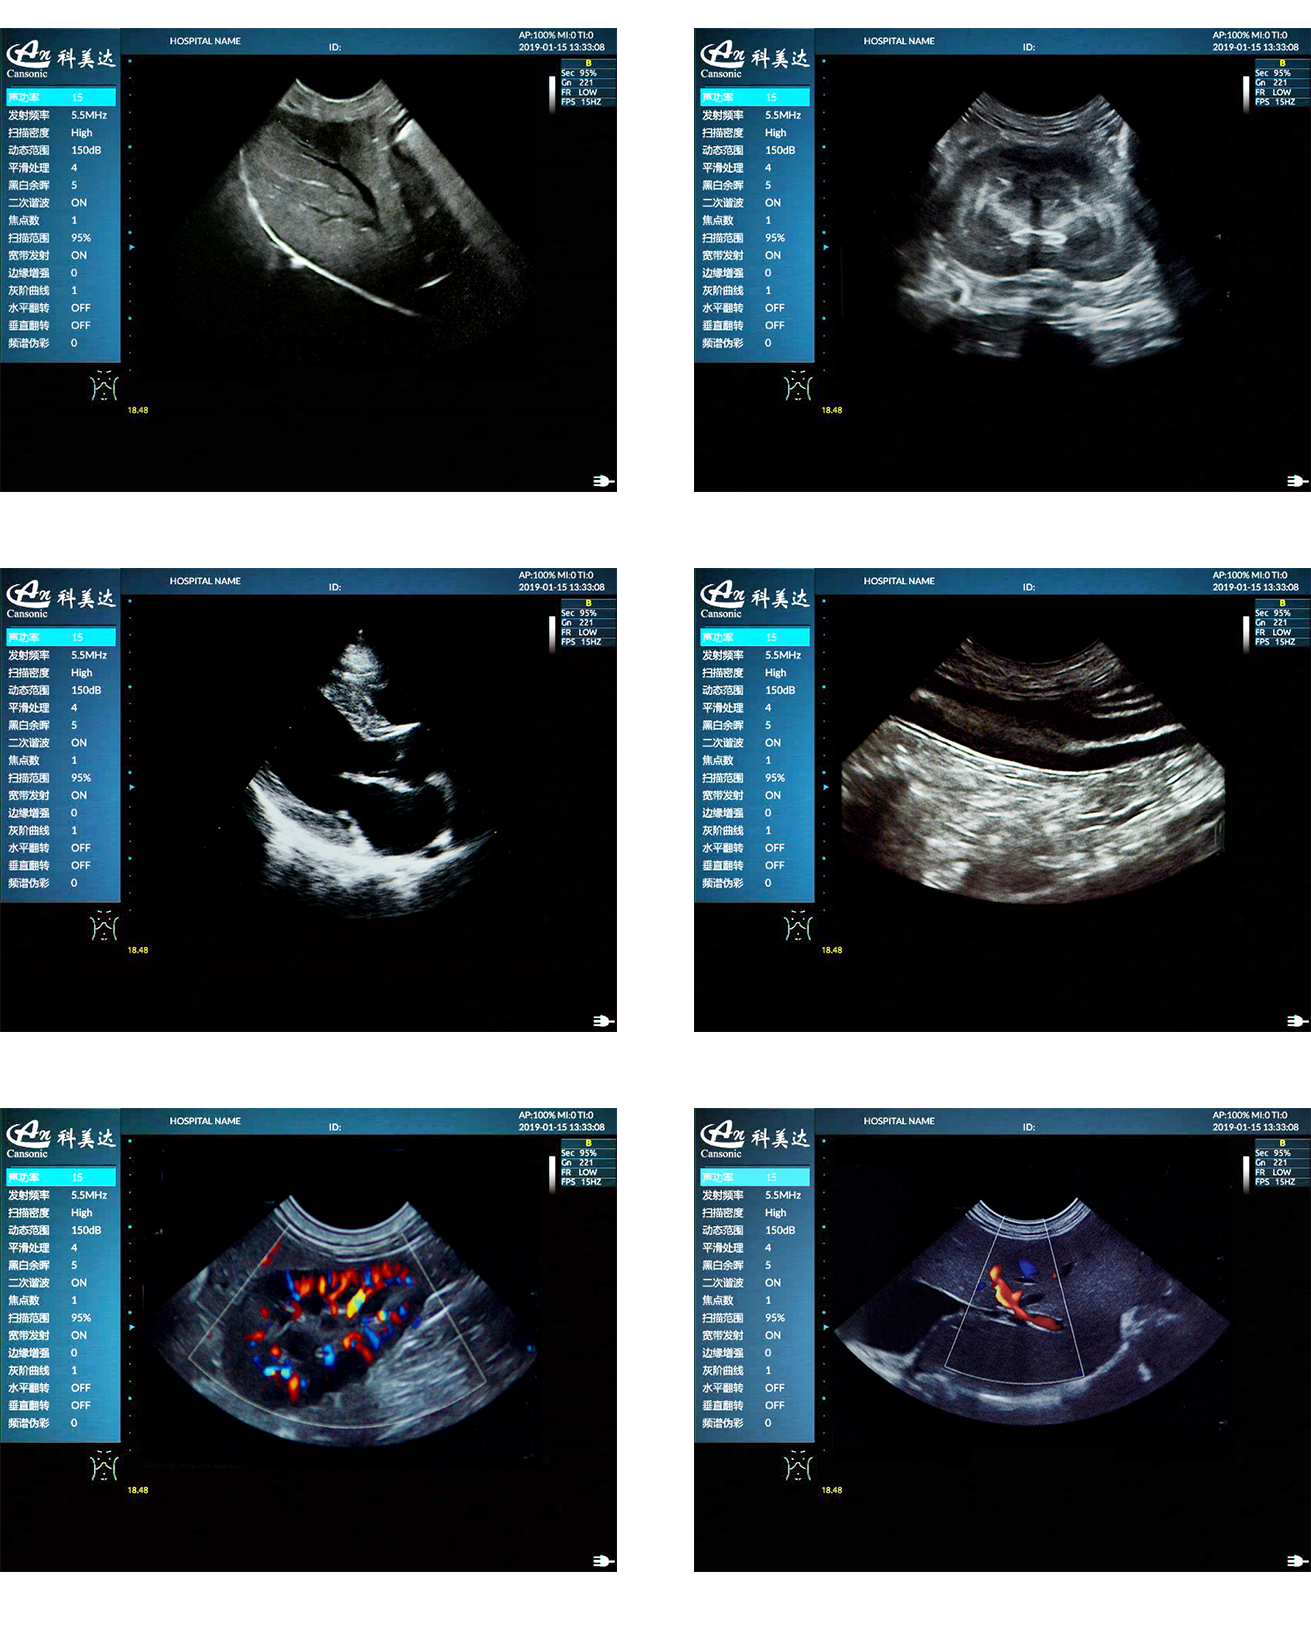

臨床圖示

1、移植高端彩超的專業技術,提供完整的動物臨床解決方案

2、專業的獸用應用軟件包,適用于狗、貓、馬、牛、羊等多種動物的腹部、生殖、血管、小器官,肌骨等檢查模式

3、先進的算法帶來清晰的穿刺針顯示效果,降低穿刺活檢操作難度,有效提高獸醫穿刺診斷信心

6、精準數字濾波技術,有效降低多普勒噪聲及運動偽像,提升血流靈敏度